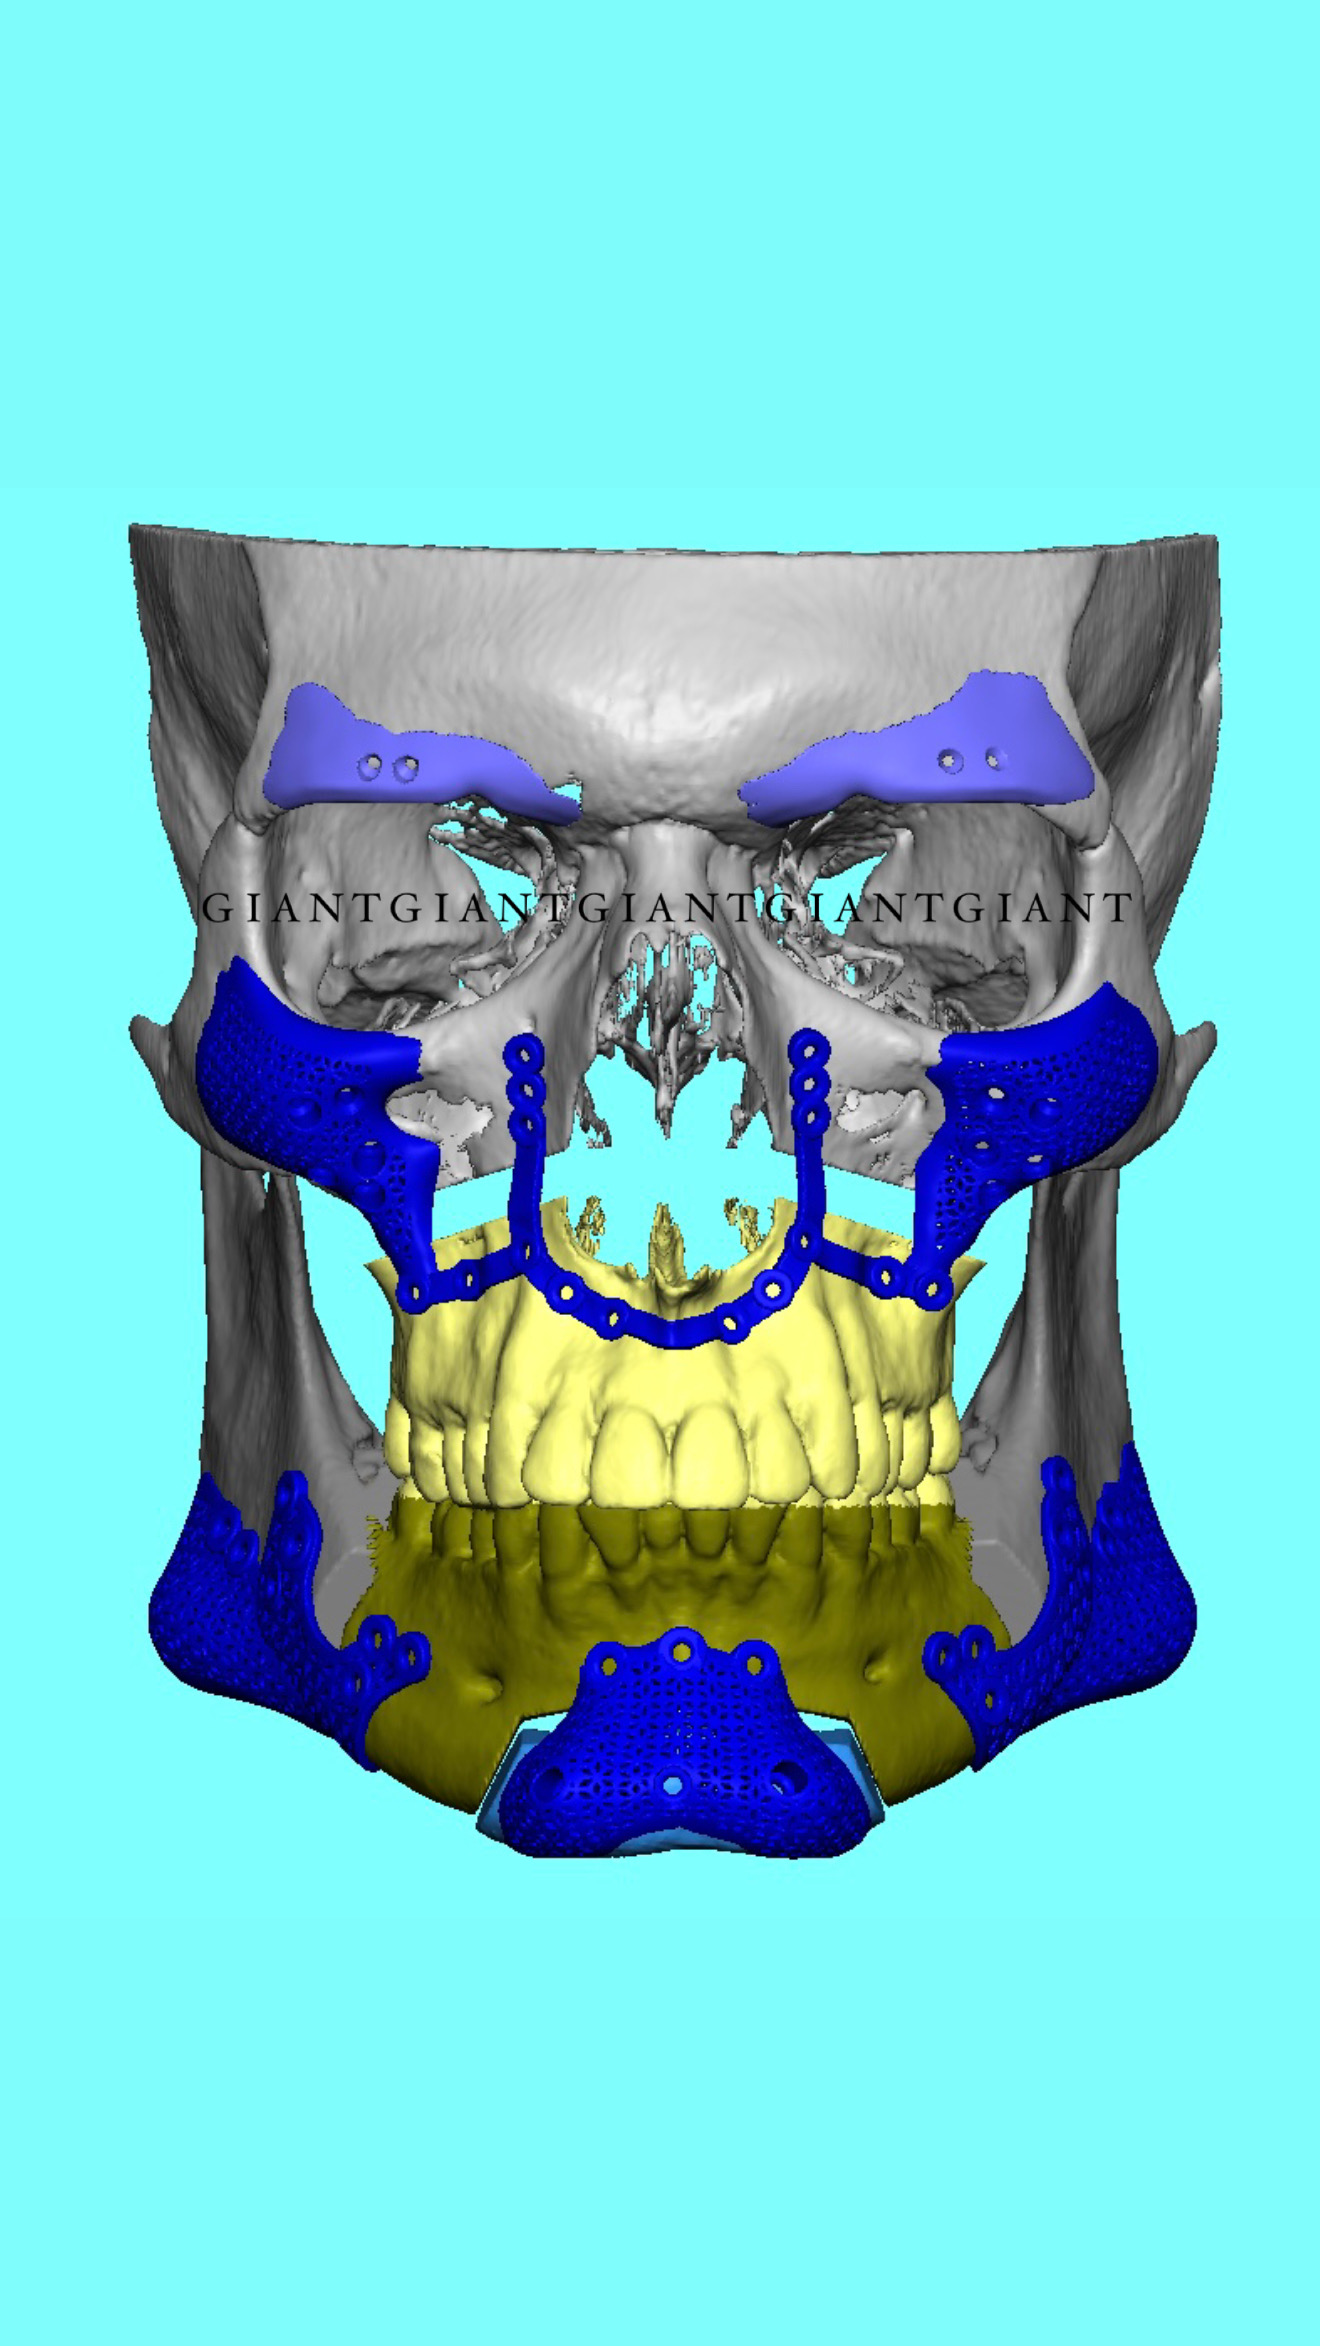

Why do surgeons like Gunson shit on custom guides and plates in the mandible? Something about not being able to predict the optimal joint position or something like that. Are they just coping and unwilling to do the extra planning required?It's annoying when people do that, because then im getting a subpar base to work on. I always wish they came for the full thing so I am not limited. Its supposed to all work together.

And no, I will not check or approve an external plan.

Because they're old dogs. Good at doing it the old fashioned way I will admit.Why do surgeons like Gunson shit on custom guides and plates in the mandible? Something about not being able to predict the optimal joint position or something like that. Are they just coping and unwilling to do the extra planning required?

but it's true that they are not reliable all the times thoBecause they're old dogs. Good at doing it the old fashioned way I will admit.

But this is the future.

View attachment 4222068View attachment 4222073